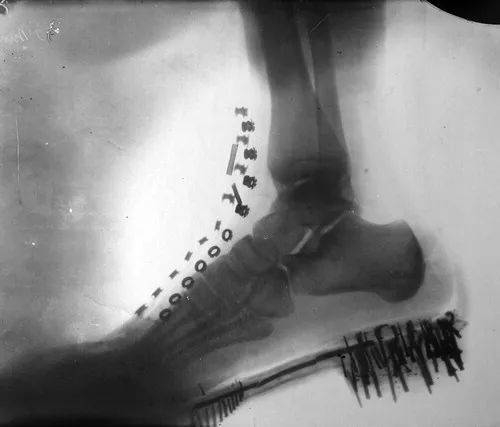

1896年,特斯拉拍摄了这张X光图像:一只脚在鞋中的阴影图

伦琴于1901年7月20日给特斯拉的信中写道:“亲爱的先生!您以美妙的放电美丽的照片使我感到惊讶,我非常感谢您。如果我知道你是怎么做到的!谨表示我特别的敬意,WC Roentgen。”